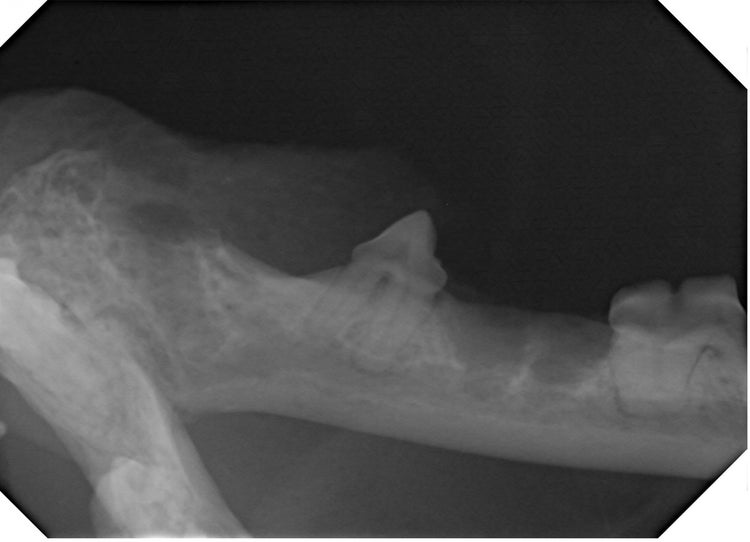

Comprehensive dental treatment was performed, including extraction of multiple teeth affected by stage four periodontal disease, treatment of retained roots and management of areas with alveolar osteitis and tooth resorption. Full-mouth radiography guided extractions and ensured complete removal of root structures. The procedure was supported by multimodal analgesia and regional nerve blocks following best‑practice guidelines.

Xray of cats tooth